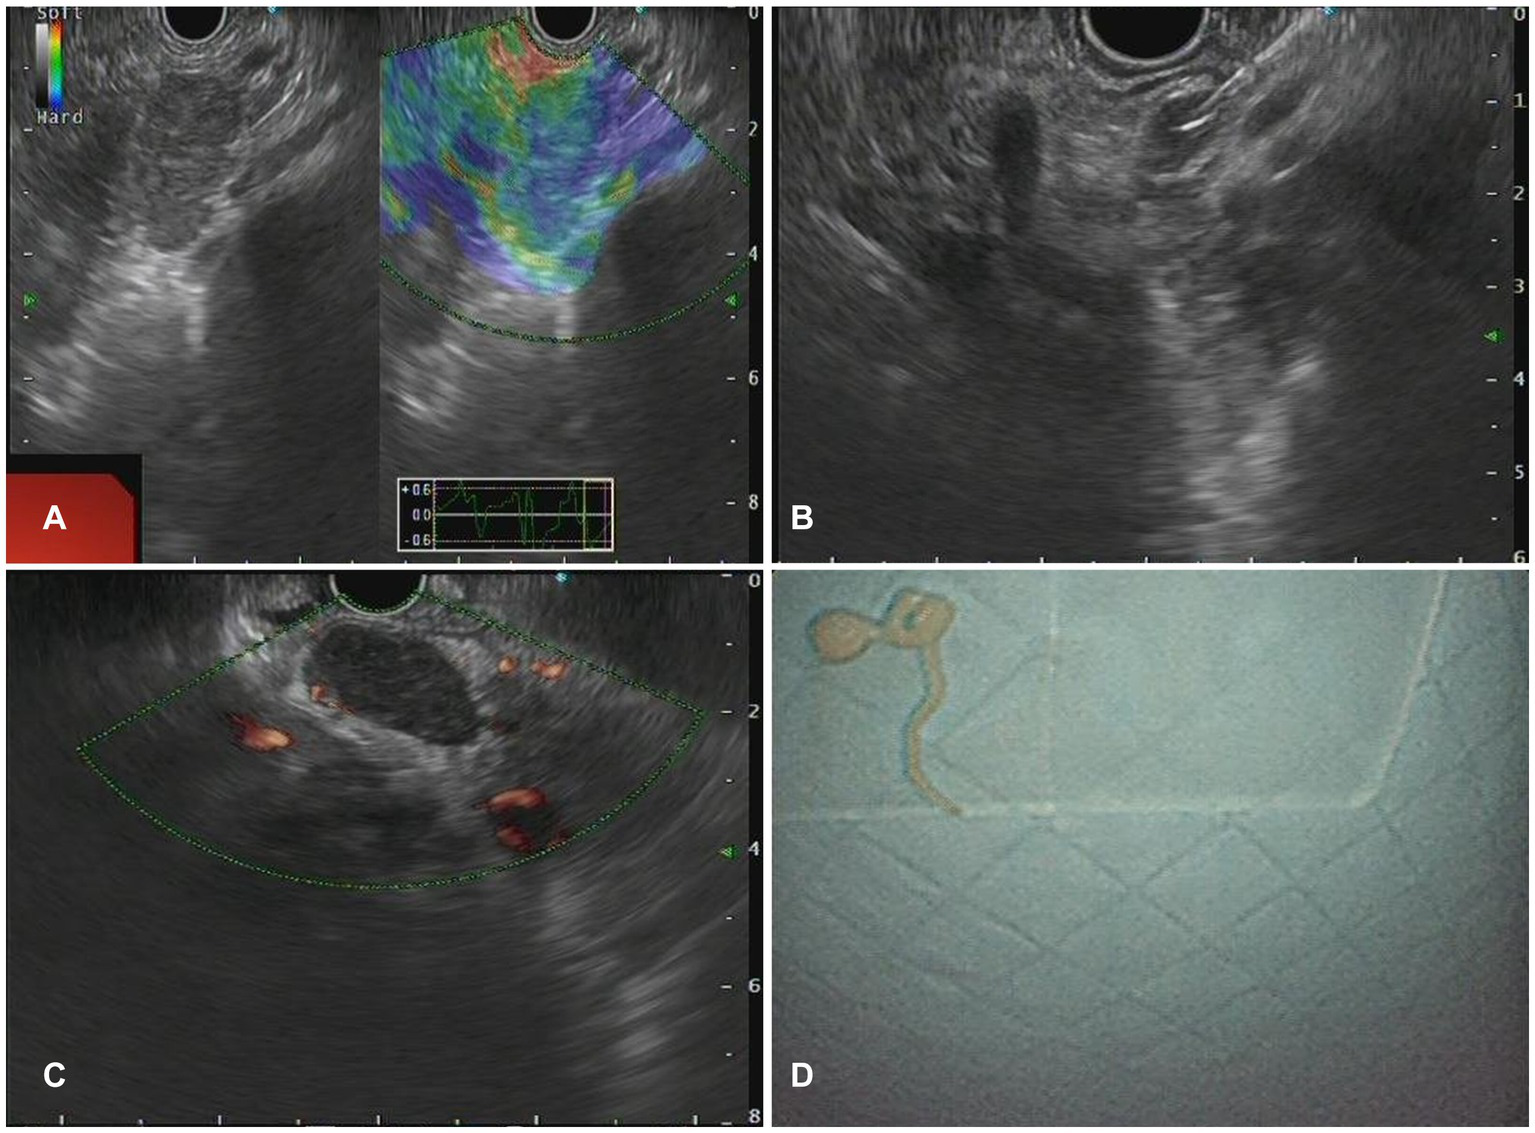

Figure 2

The Endoscopic ultrasonography image features of Benign Lymphadenopa-thy in patients. (A) A case of reactive lymphadenomegaly. Multiple hypoechoic nodules, some of which were fused into clusters, with a hard texture on elastography were observed during EUS. (B) A case of sarcoidosis. A low echo lymph node shadow was identified in the hepatic portal area on EUS, with no obvious blood flow signal in the lesion on Doppler, and elastography indicated a hard texture of the lesion. (C,D) One case of lymph node TB. EUS showed clear boundary lymph nodes with regular morphology (C) and pus in the specimen obtained from fine needle aspiration of a lymph node (D).